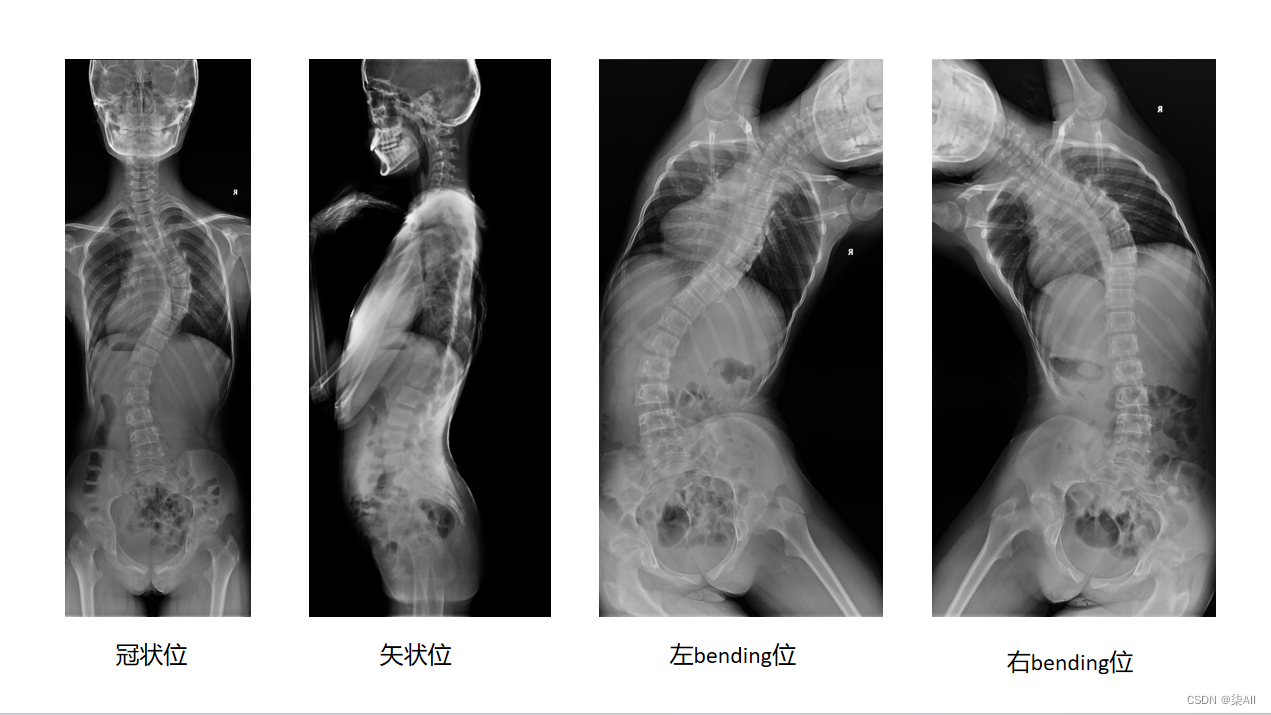

脊柱数据有四方位的数据,冠状位、矢状位、左bendin、右bending

1、数据显示如图

2、需要标注的关键点(冠状位、左右bending位)

冠状位(一共是标记72个关键点)

左右bending(一共也是标记72个关键点)

左bending和右bending是一样的,这里就做一个示范